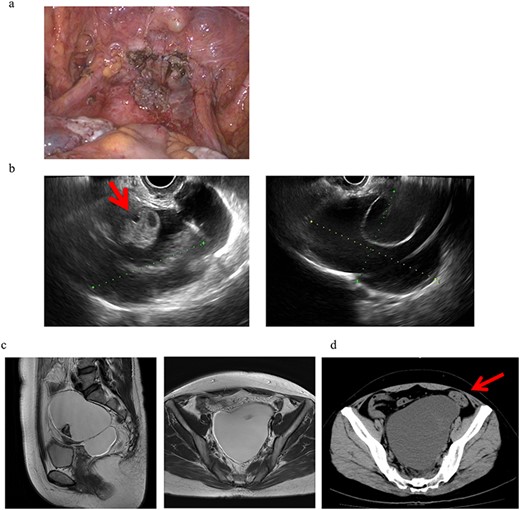

A 43-year-old woman, gravida 2, para 2 was diagnosed with uterine myoma and underwent TLH. No abnormal intra-abdominal findings, such as adhesions, endometriosis or ovarian cysts, were detected. As shown in Fig. 2a, no abnormal findings, such as adhesions, were detected at the end of surgery or 2 months later.

Clinical findings of case 2 (before surgery for PIC). (a) Findings at the end of TLH. No abnormal findings were detected. (b) An US image of PIC. The major axis was 95 mm. An ovary with a normal appearance was observed within the multilocular cyst.

Four years and 6 months after surgery, she presented with lower left abdominal pain. A multilocular cyst, measuring ~10 cm, was detected on the vaginal stump by transvaginal US (Fig. 2b). Since the cyst was considered to be causing her symptoms, emergency surgery was performed. Adhesions were observed in the left adnexal region, and a clear yellow liquid was retained in the cavity formed by the adhesions (Fig. 3). The adhesions were removed by laparoscopic surgery and left adnexal excision was performed, which ameliorated her symptoms.